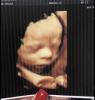

Кто делал 4D фото на третьем скрининге? Получилось ли хорошо?

Девочки кто делал 4д фото на третьем скрининге? Получилось ли хорошо интересно

31 неделя